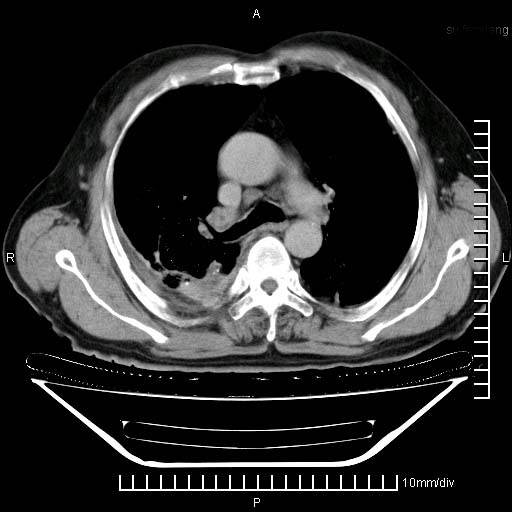

标题: CT24043:胸部增强:男性,60岁

既往肺结核,近10几天,咳嗽,咳痰,右侧胸痛,疼痛较明显,右上肺斑块考虑结核灶胸膜粘连,增强,可惜动脉期没有定好,未见强化,可延迟4分后又见较明显强化,中心见低密度影,如果说结核是边缘强化,可这个灶强化的面积挺大的,让人很挠头。

强化的组织可能是膨胀不全的肺组织或炎性肉芽组织。

1)两肺继发性肺结核。2)右侧胸膜增厚+少量胸腔积液。